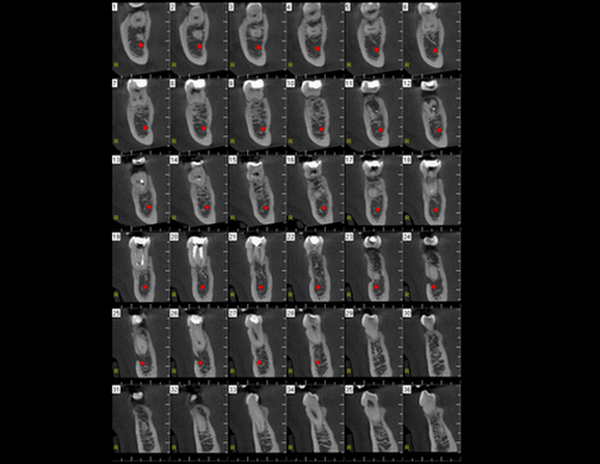

A Tomografia Computadorizada pela técnica do feixe cônico/cone beam (CBCT) introduziu um novo conceito de tomografia computadorizada na região bucomaxilofacial, que por meio da rápida aquisição volumétrica produz imagens com altíssimo grau de definição e fidelidade, além da redução na dose total de radiação emitida ao paciente.

Além disso, ocorre a minimização dos artefatos de imagem em relação à TC médica, o que torna possível a realização de imagens com qualidade diagnóstica e precisão sub-milimétrica, mesmo na presença de estruturas metálicas (restaurações, pinos/núcleos, aparelhos ortodônticos).